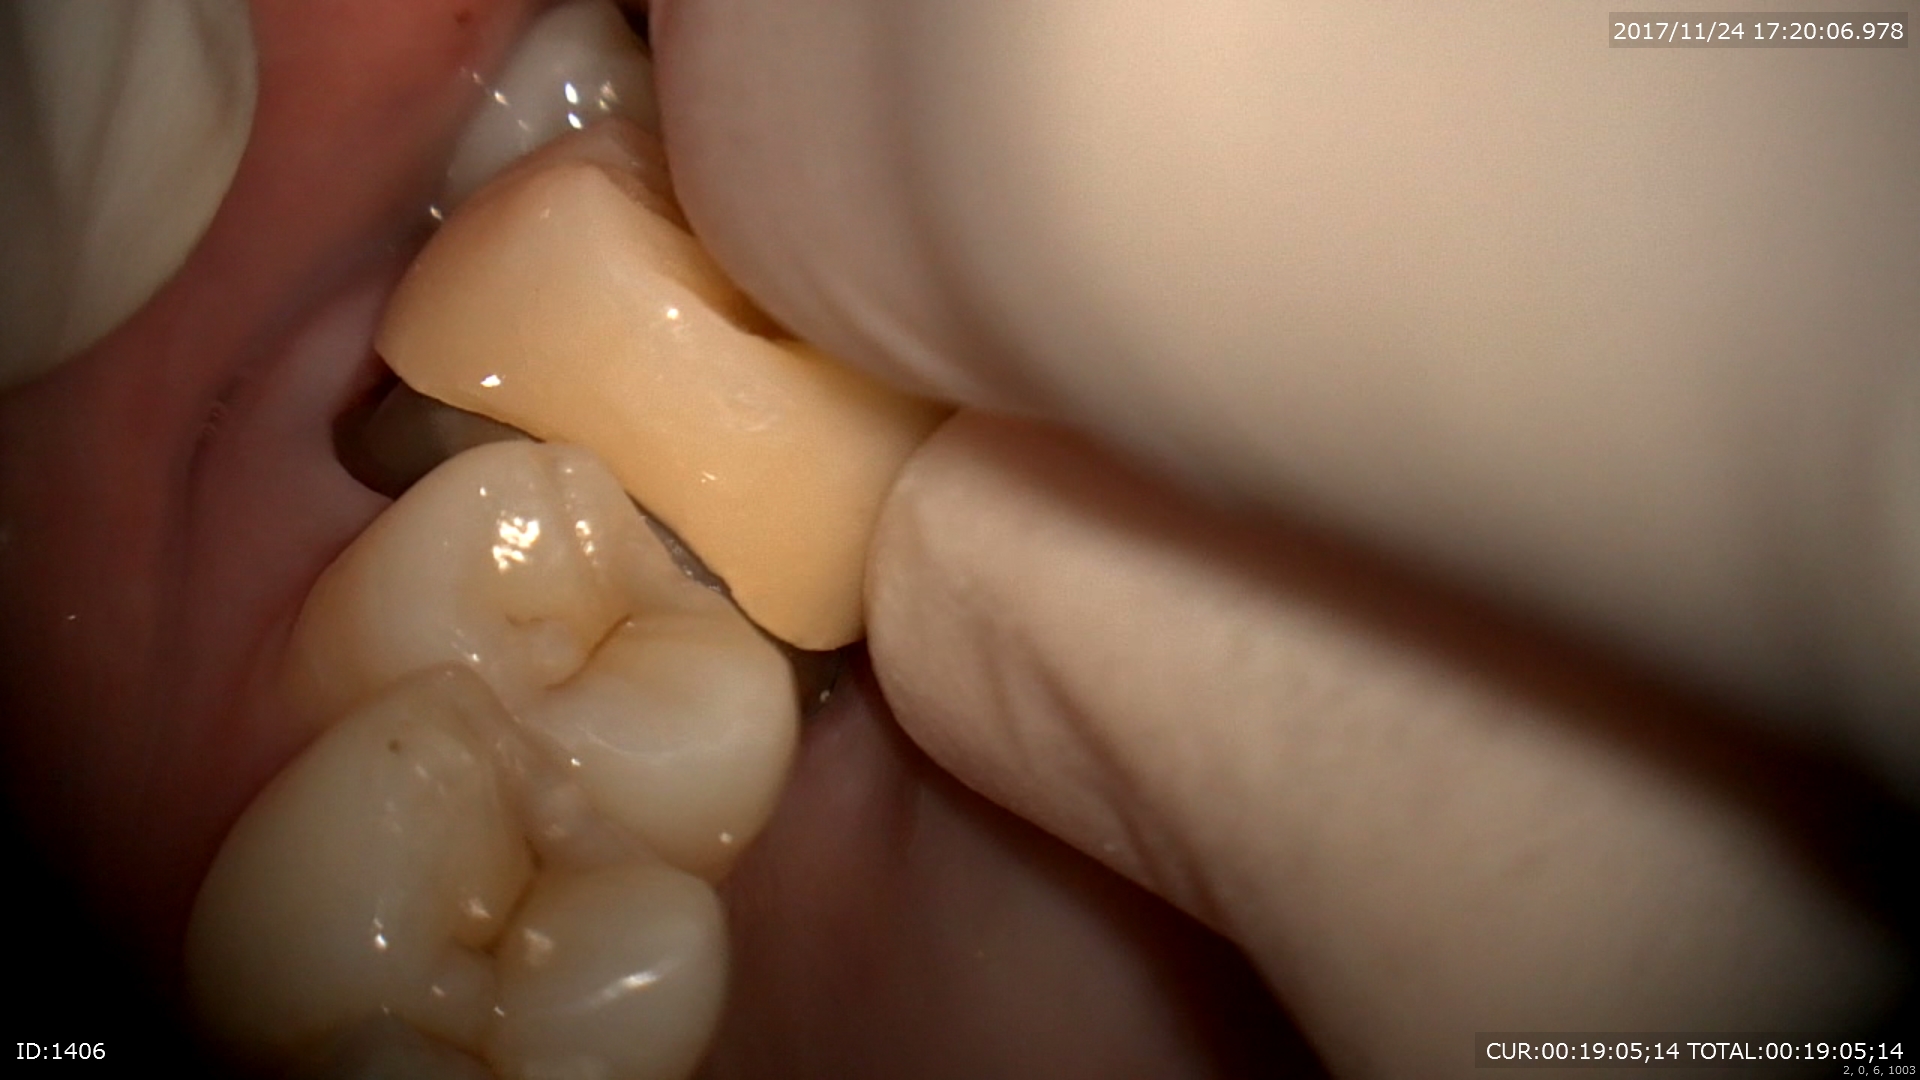

ハイブリットクラウンの装着

仮歯を外して歯肉の炎症がないか見ます。当院では仮歯を入れないでの治療は一切行いません。1つ1つの工程には重要な意味があり歯肉の状態やかみ合わせの関係、細菌侵入のリスクを考え仮歯を入れます。

前回

本日

試適をして

装着